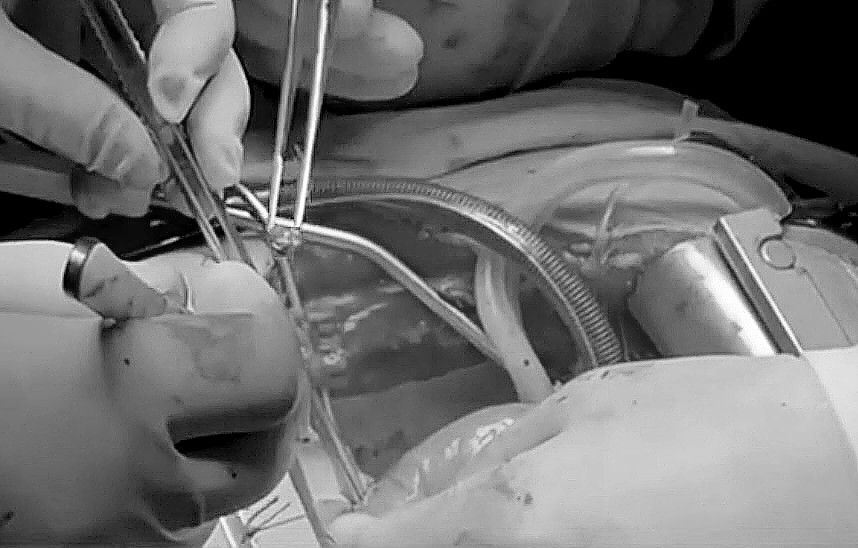

Момент извлечения осколка из сердца